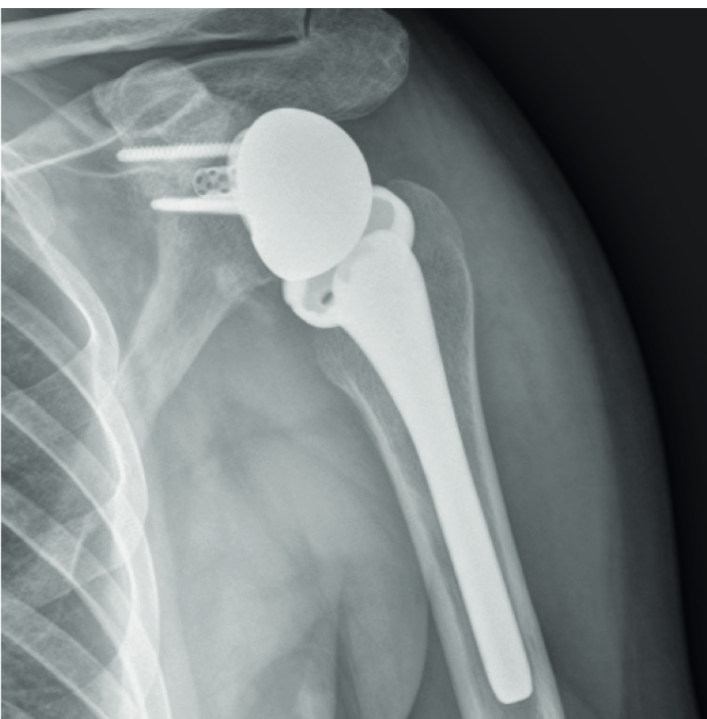

Alessandro Donà | Giuseppe Porcellini | Valentina Passarino | Alberto Brigo | Andrea Giorgini | Gian Mario Micheloni | Rocco Bonfatti | Luigi Tarallo IntroductionLipomas